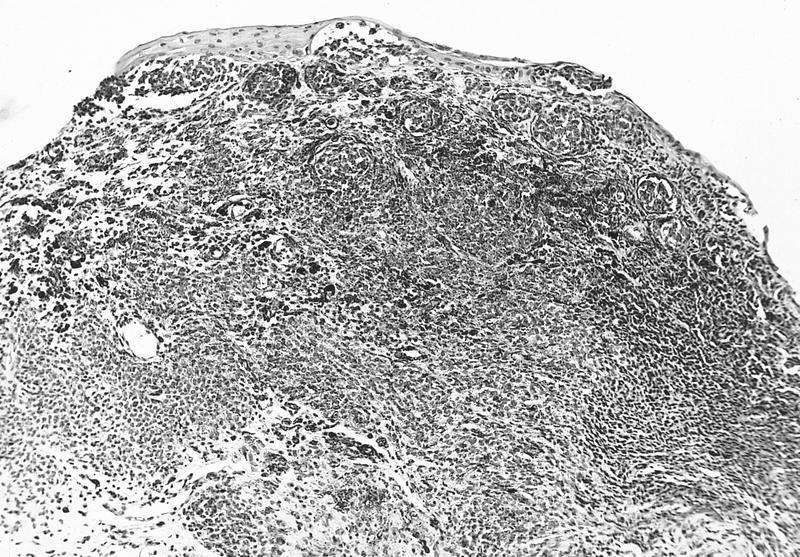

- Nevomelanocytes organized into intraepithelial nests of oval cells (type A), sheets of oval to cuboidal cells (type B), and spindled cells in subepithelium (type C)

- Often (50%) with solid and prominent cystic inclusions of conjunctival epithelium and chronic inflammatory infiltrate

- Compound (70 - 78%):

- Most common, nevi cells in epithelium and subepithelial connective tissue

- Cells have cysts lined by cuboidal and goblet cells and intranuclear inclusions

- May have large pigmented cells with prominent basophilic nucleoli

- Usually mixed inflammatory cells

Cystic compound nevus: